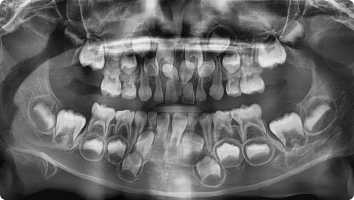

앞니 한가운데 잇몸 뼈 속에 필요 없는 치아가 숨어 있는 경우를 말합니다.

이 치아는 앞니 배열을 방해하거나 영구치가 나오지 못하게 할 수 있어,

보통 조기에 발견하면 발치해 주는 것이 좋습니다.

- 국소마취 하에 잇몸을 살짝 열고 숨어 있는 과잉치만 조심스럽게 제거합니다.

- 이후 잇몸을 봉합해 안전하게 회복되도록 합니다.

수술은 짧은 시간에 안전하게 진행되며, 대부분 아이들은 수술 후 큰 불편 없이 회복합니다.